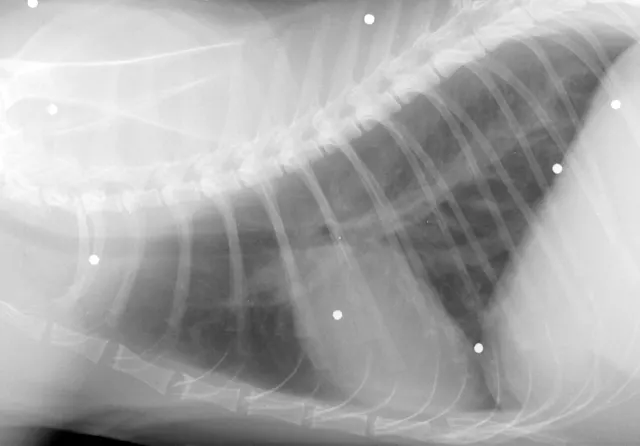

Cardiac ultrasonography is much more useful in cats than in dogs, simply because worm size relative to the size of pulmonary vasculature is greater in cats. Heartworms are most often found in the pulmonary arteries, requiring special imaging techniques. They may be visualized less frequently in the right ventricle, right atrium, or anterior or caudal vena cavae. The sensitivity approaches 80% for experienced sonographers. The adult heartworm appears as a double-lined structure as sound waves rebound from the cuticle. Echocardiographic quantification of worm burden is difficult.